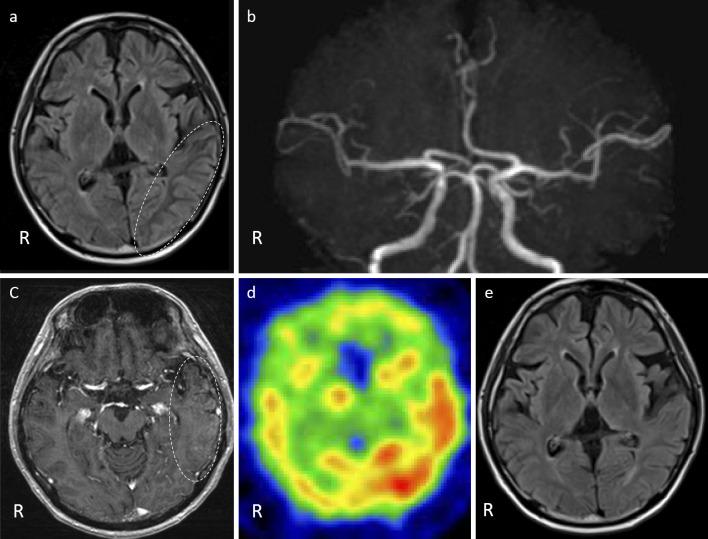

A 36-year-old man with a history of irradiation for acute lymphoblastic leukemia developed headache with cortical dysfunction lasting for 4 weeks. The clinical features were consistent with stroke-like migraine attacks after radiation therapy (SMART) syndrome. Six months later, he developed cerebral infarction due to occlusions of the left anterior and middle cerebral arteries. This is the first case report describing SMART syndrome followed by severe cerebral infarction. Although an association between the two episodes was not assumed, this case indicates that protective therapies against infarction might need to be considered for patients with SMART syndrome.

一名36岁男性,有急性淋巴细胞白血病放疗史,出现头痛伴皮质功能障碍,持续4周。临床特征符合放疗后类卒中偏头痛发作(SMART)综合征。6个月后,他因左侧大脑前动脉和大脑中动脉闭塞发生脑梗死。这是首例描述SMART综合征后发生严重脑梗死的病例报告。尽管未假定这两个事件之间存在关联,但该病例表明,对于SMART综合征患者可能需要考虑采取预防梗死的治疗措施。